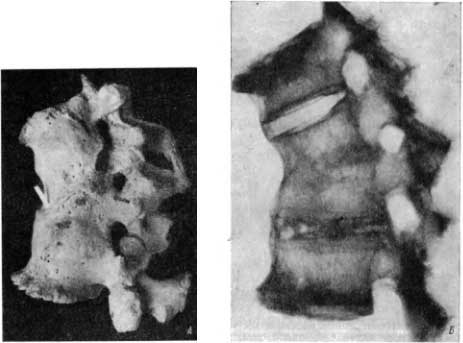

Нижняя четверть V грудного и верхняя треть тела VI грудного позвонков разрушены (рис. 23, А). Деструкции подверглись также соответствующие реберно-позвоночные суставы с обеих сторон. Это — туберкулезный спондилит со значительным разрушением двух смежных позвонков без репараторных и реактивных изменений.

Рис. 23. А — туберкулезный спондилит без репаративных изменений; Б — туберкулезный спондилит с клиновидной деструкцией тел двух смежных позвонков без образования костного блока.

Другая находка относится к эпохе железа (из погребений у оз. Иссык-Куль). Скелет принадлежит мужчине в расцвете сил. Имеются клиновидная деструкция тел XII грудного и I поясничного позвонков, проявления артроза на суставных фасетках в результате статической нагрузки в условиях углового кифоза и деформирующий спондилоз в области тел XI грудного и II и III поясничных позвонков. Перед нами картина резко выраженного туберкулезного спондилита с поражением тел двух смежных позвонков без тенденции к образованию костного блока (рис. 23, Б).